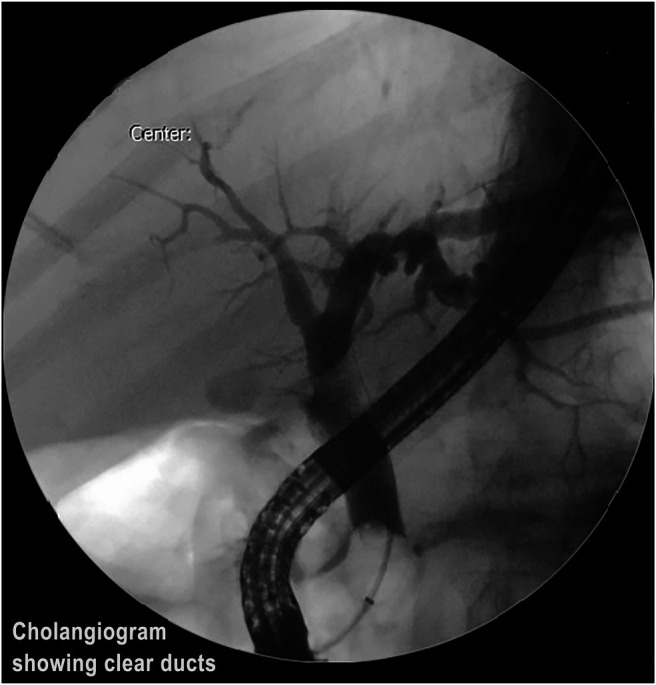

The stone was grasped with the Dormia basket, and multiple attempts to crush and retrieve it remained unsuccessful, resulting in the entrapment of the Dormia basket with the impacted stone (Figure 2). Balloon sphincteroplasty to 16 mm was performed for extraction of the entrapped basket and stone with no success (Figure 3). Subsequently, it was decided to use a novel technique of cholangioscope-guided EHL to dislodge and retrieve the entrapped basket. Basket wires were cut from the proximal end to release tension for the facilitation of retrieval. A single-operator intraductal cholangioscope was advanced with direct visualization of the stone and entrapped basket. EHL was performed for stone fragmentation (Figure 4). After fragmentation, a wire-guided extraction balloon was placed within the entrapped basket and fragmented stones. The extraction balloon was then inflated to 15 mm, which released the entrapped wires, and subsequently, the basket was retrieved successfully (Figure 5). Stone fragments were retrieved with the extraction balloon, and an occlusion cholangiogram confirmed clear ducts (Figure 6). The patient was discharged on the same day with no procedure-related complications.